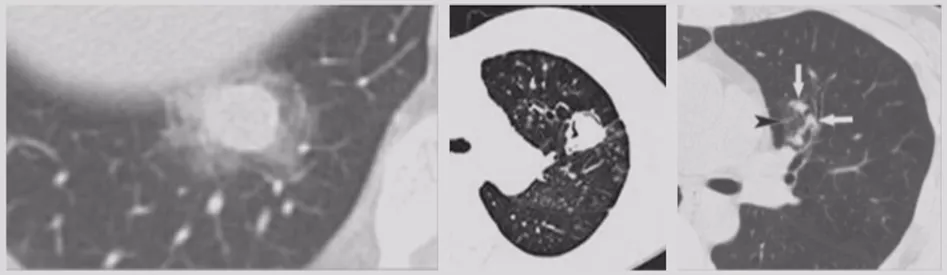

小细胞肺癌

小细胞肺癌以中央型多见,但是也有少数为周围型病灶。多为单个实性结节或肿块,可见分叶、毛刺、血管集束征、胸膜牵拉征。实际上我们很难从影像学上判断出小细胞肺癌的病理类型,往往是活检或者手术以后才能证实。如下图示,这属于I期的小细胞肺癌,进行手术的效果非常好。所以对于周围型小细胞肺癌,如果在结节很小的时候判断出来就做了手术,疗效非常好。我们知道小细胞肺癌是肺癌中治疗效果最差的,恶性程度是最高的。如果早期手术,仍然能够起到很好的效果。

肺曲霉菌病

肺曲霉菌病可以表现为单发或多发的结节或肿块,边缘模糊,有的聚集成簇。感染早期可见胸膜下密度增高的结节影,病灶周围可出现晕征。发病10-15d后,肺实变区液化、坏死,可见空腔阴影或空气新月征。所以肺结节的鉴别诊断还要考虑是否存在曲霉菌感染。